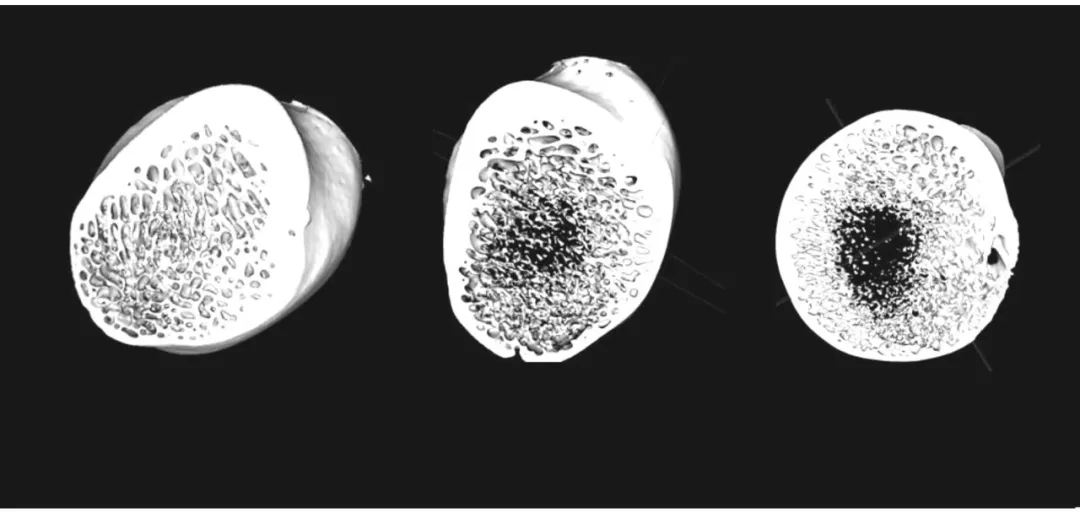

1 骨小梁结构

显微 CT 技术可以清晰地展示骨小梁的形态、分布和结构特征以及厚度、间距、数量等指标。

Neoscan 台式显微CT 扫描骨骼,揭示内部骨小梁结构

假手术组(左)与去势 4 个月组(中) 及去势 12 个月 组(右) 腰椎松质骨的三维重建图像。图片显示,去势 12 个月组的骨小梁较其他两组明显稀疏,孔隙率增加,水平方向骨小梁减少,局部有较大的骨小梁空隙形成。图片源于文献【1】。

假手术组(左)与去势 4 个月组(中)及去势 12 个月 组(右)股骨颈处松质骨的三维重建图像。图片显示,去势 12 个月后,股骨颈处松质骨有空腔形成,骨小梁明显变细,皮质骨壁变薄。图片源于文献【1】。